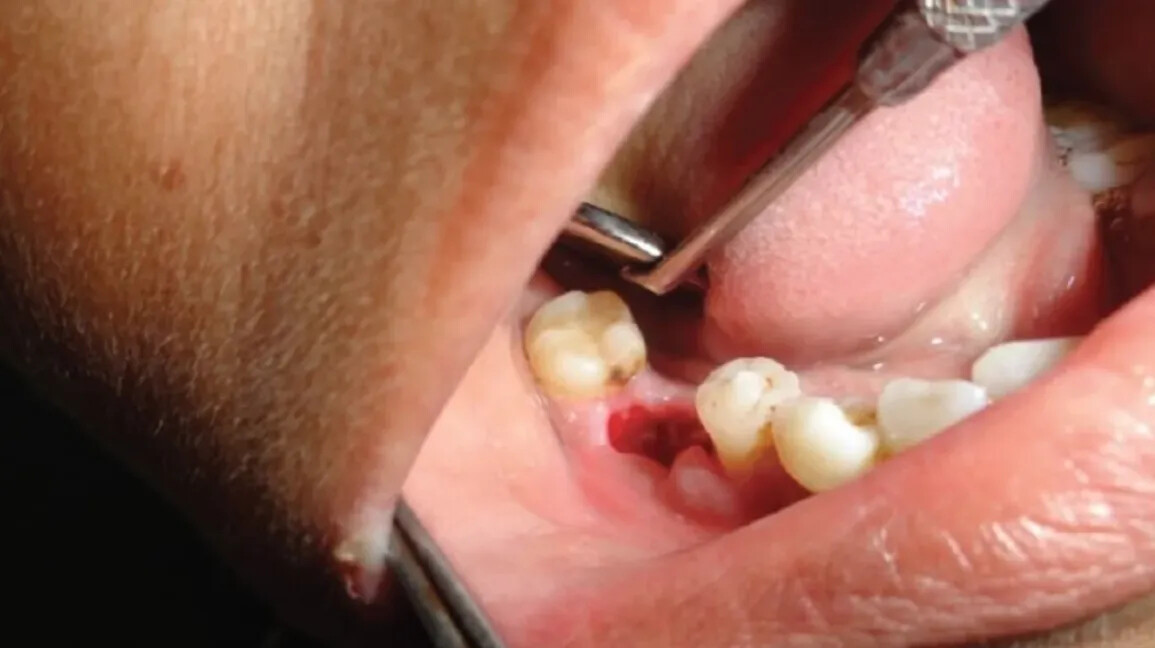

Dry socket, also known as alveolar osteitis, is an uncomfortable dental condition that sometimes occurs after a tooth extraction or wisdom teeth removal.

When you have your tooth extracted, you develop a blood clot over the removal site to protect the nerves and bone beneath the detached tooth. Typically, the clot forms and stays in place until your gums have healed and are back to normal.

A dry socket occurs when the blood clot at the site of the tooth extraction fails to develop. In some cases, the clot can become dislodged before the wound is healed. It’s important to prevent dry socket from happening as it can be very uncomfortable, and it can delay the healing of gums and your overall mouth.